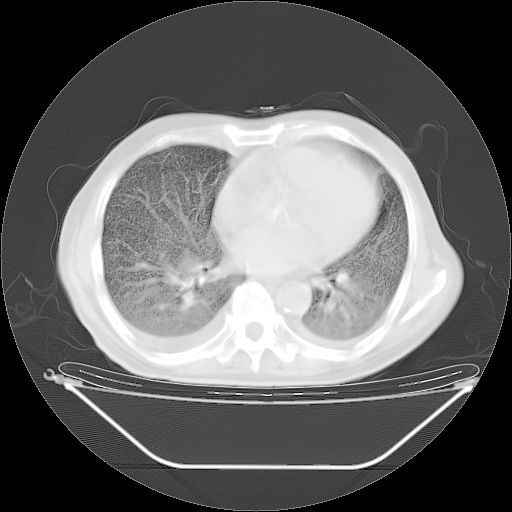

今天复查肺部CT,发现双肺广泛磨玻璃样改变。所以我把3月19日和5月9日相隔50天的肺部CT上传。请大家会诊。

5月9日肺部CT(在4月27日齐鲁医院肺部CT描述部分肺组织磨玻璃样改变,12天后肺组织广泛磨玻璃样改变)

大致读了系列胸部CT:纵隔窗无明显异常,肺窗:从4、27至今:主要是双肺中下野外带可见毛玻璃样改变,目前处于急性肺泡炎阶段,至于原因考虑1、结替组织或胶原血管性疾病所致?2、恶性疾病如恶组在肺部所致的表现或细支气管肺泡癌?3、药物或其它原因如肺蛋白沉着症所致肺泡炎目前不太可能?总之,明天就去请我院的呼吸科、感染科、血液科和临免专家会诊哈。